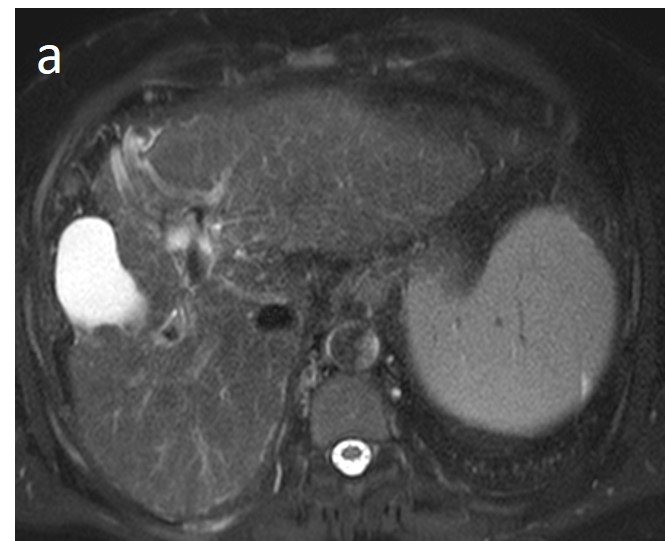

As mentioned before, the radiological hallmark that enables a confident non-histological diagnosis of HCC is the combination of hypervascularity on the arterial phase and hypoperfusion on the portal phase; as with CT, this “wash-in/wash-out” pattern is indispensable on MRI as well. According to the LI-RADS criteria, no lesion without hyperenhancement on the arterial phase can be definitely characterized as HCC; hyperenhancement has to be “non-rim”, i.e., not predominantly peripheral (in order to differentiate from metastases or cholangiocarcinoma) [51]. However, up to 40% of HCCs show no hypervascularity on the arterial phase, and these mainly represent early or poorly-differentiated HCCs [131,132]. Moreover, 40–60% of small HCCs lack wash-out during the portal phase [133,134] (Figure 10). Additional major and ancillary features are employed to help characterize the lesion and assign a LI-RADS category to it.

Figure 10. Evolution of a cirrhotic nodule into HCC. No suspicious lesions are identified on the T2 (a) and DWI (b) sequence of this 66-year-old man with cirrhosis due to hepatitis B infection. On the follow-up scan, performed 3 months later, increased T2 signal (c) is now observed in a nodule in segment V, which is associated with diffusion restriction (arrow) (d). After contrast administration, arterial enhancements (e) without delayed wash-out (f) are seen; absence of wash-out is frequent in early HCCs.